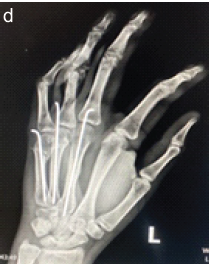

Outcome of Non-thumb Metacarpal Shaft Fractures Treated by Two Different Techniques – K Wire and Herbert Screw Fixation: A Comparative Single Centre Study

Dinesh Raj Selvaraj , Makesh Ram Sriraghavan , Naveen Venkidusamy , Poornima Kumararaja